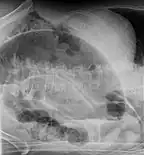

Coffee bean sign in a person with sigmoid volvulus

After taking a thorough history, the diagnosis of colonic volvulus is usually easily included in the differential diagnosis. Abdominal plain x-rays are commonly confirmatory for a volvulus, especially if a coffee bean sign is seen. These refer to the shape of the air-filled closed loop of colon which forms the volvulus. Should the diagnosis be in doubt, a barium enema may be used to demonstrate a "bird's beak" at the point where the segment of proximal bowel and distal bowel rotate to form the volvulus.